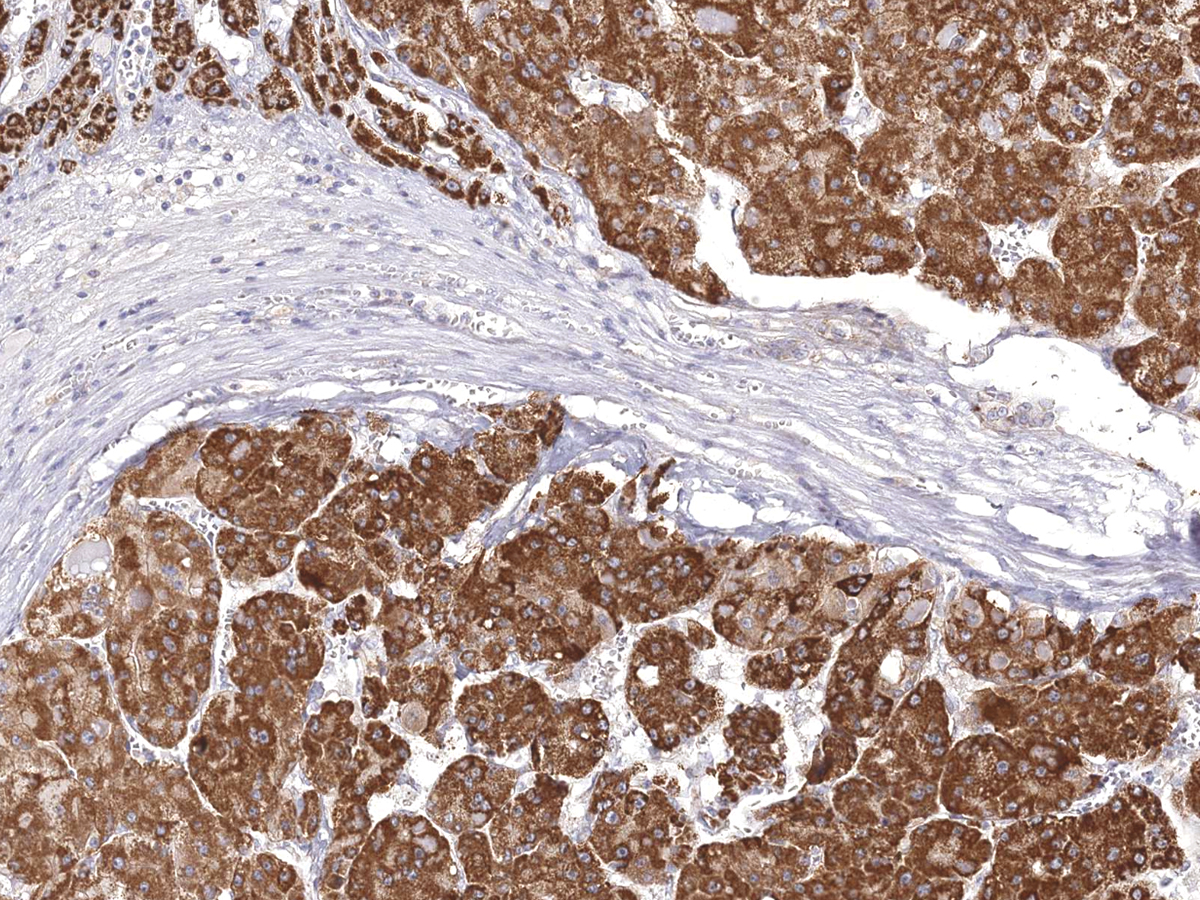

图片:

DOG1 [P1042] on Liver Cancer